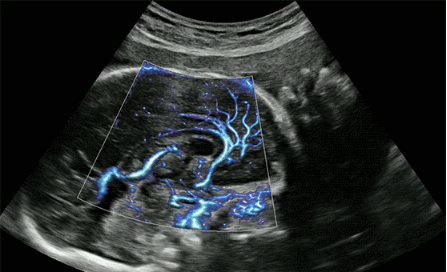

CrystalLive?是三星最新的超聲成像引擎,同時(shí)增強(qiáng)了2D圖像處理能力、3D渲染能力和彩色信號處理能力,能夠在復(fù)雜情況下提供出色的圖像性能,具備檢測外周血管、微循環(huán)血流的能力。